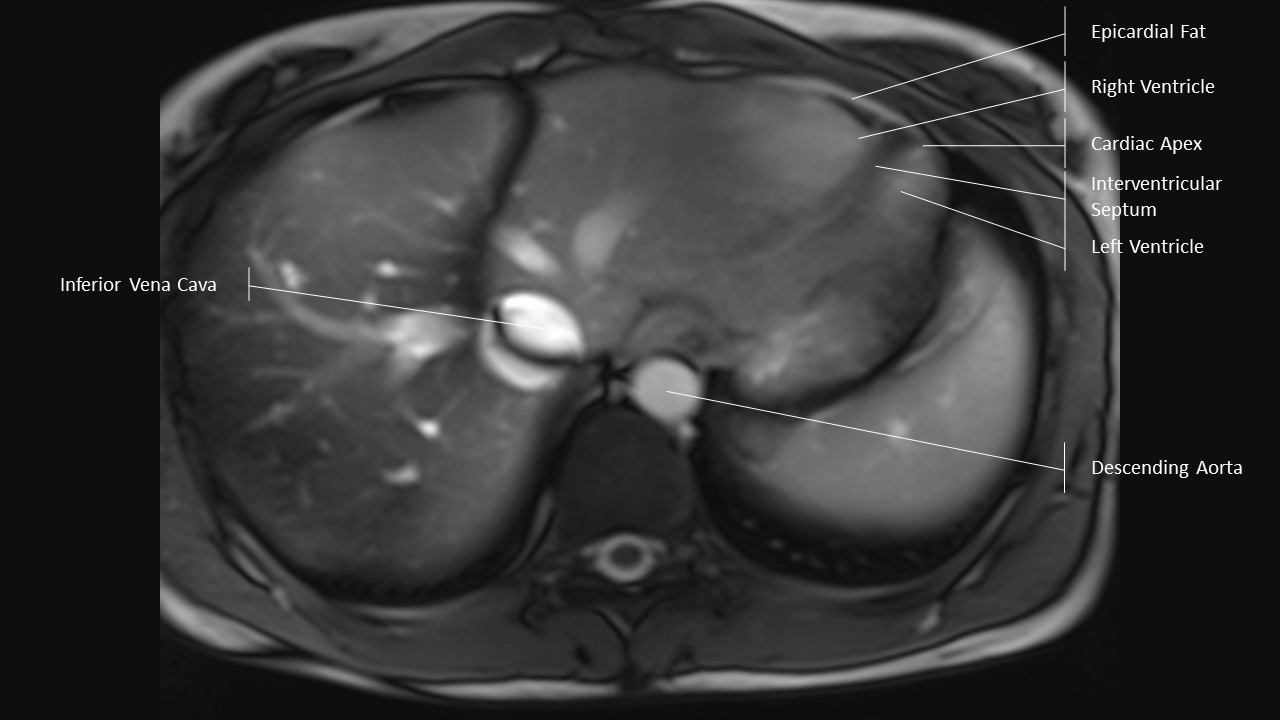

Axial Series

Extracardiac Labels